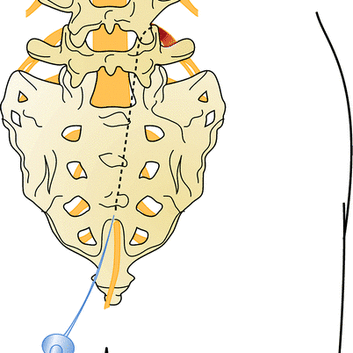

척추 통증의 원인이 되는 돌출 된 디스크나 좁아진 협착이 있는 경우 통증의 원인은 신경 주위의 유착과 부종 및 염증입니다. 경막외 신경성형술은 꼬리뼈에 있는 척추관으로 통하는 구멍으로 직경 1mm 미만의 카테터를 삽입하여 디스크와 협착증이 있는 부위까지 접근시켜 물리적으로 유착을 박리하고 화학적으로 염증과 부종을 줄여줍니다.